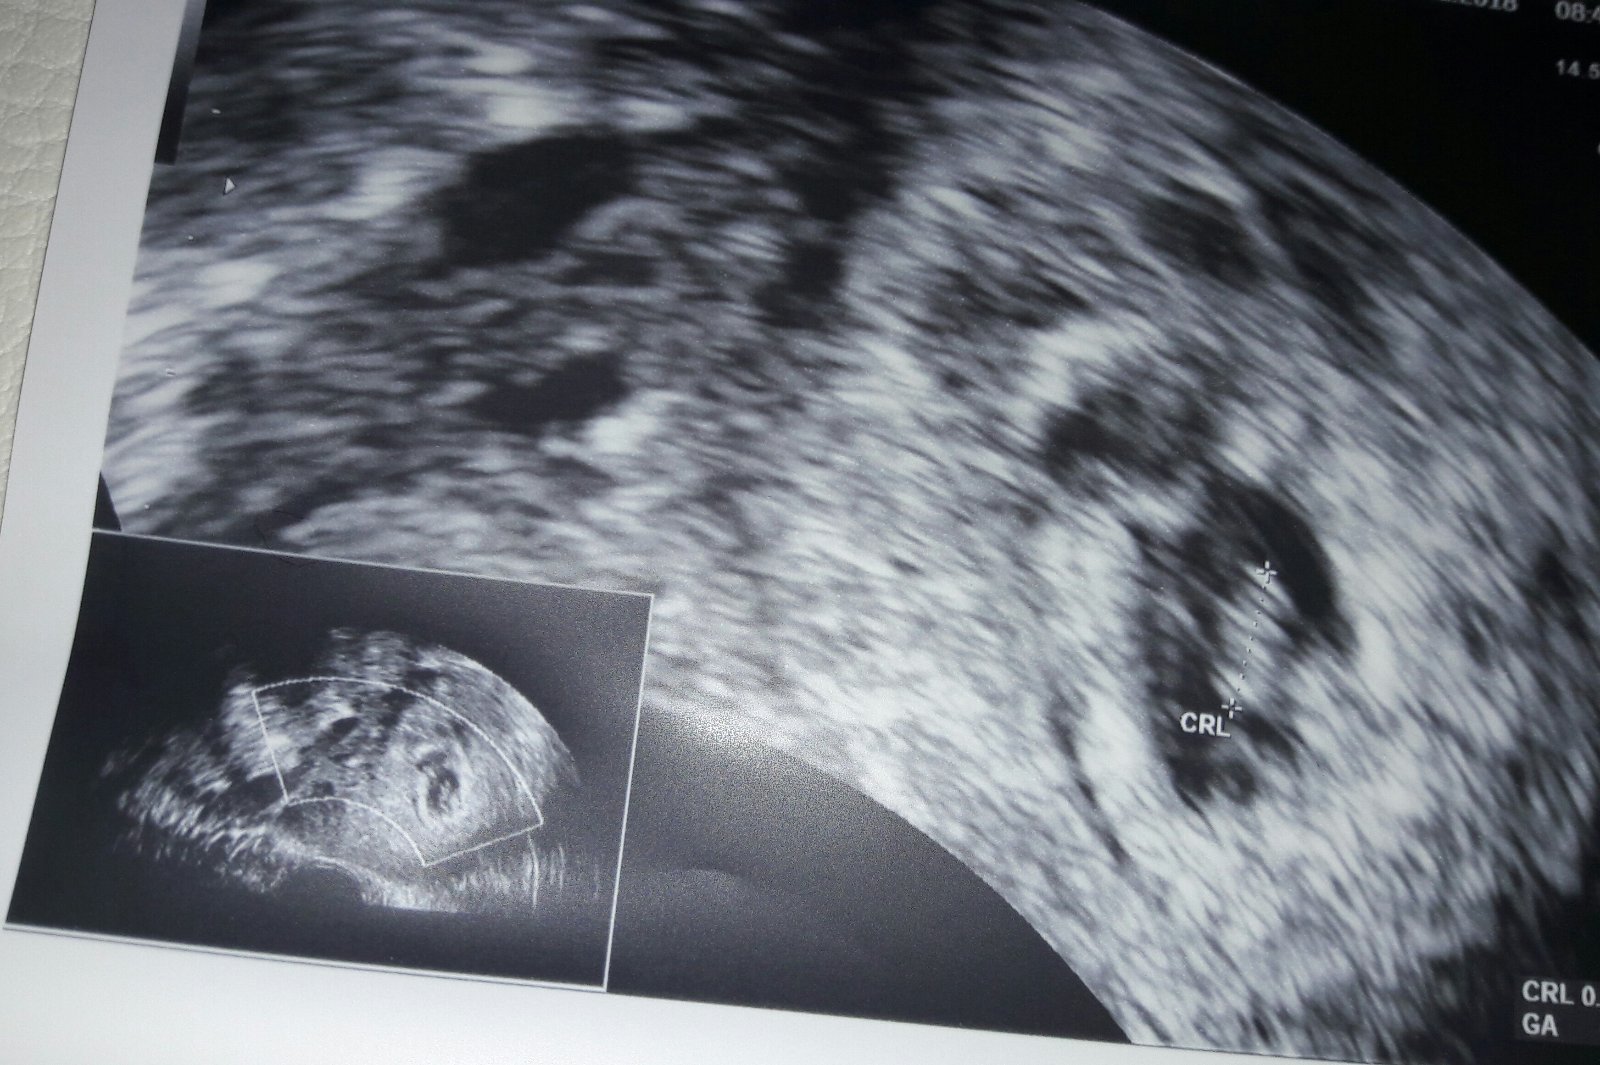

Dnes proběhl 1.ultrazvuk a videla jsem prcka i srdicko.